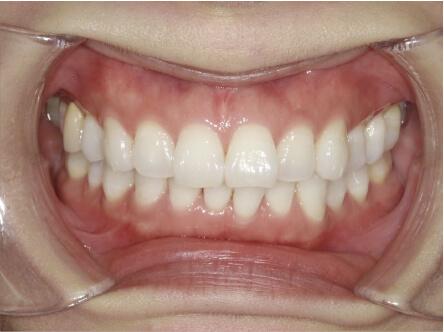

過蓋咬合の症例

15歳

/

女性

相談内容

前歯と前歯が噛んでいない

カウンセリング・診断結果

過蓋咬合

治療内容・方法

全額アライナー矯正

術後の経過・現在の様子

クリアライナー使用

治療のリスク

痛み・歯根吸収・歯肉退縮・虫歯・後戻り

費用・治療期間

830,000円、2年